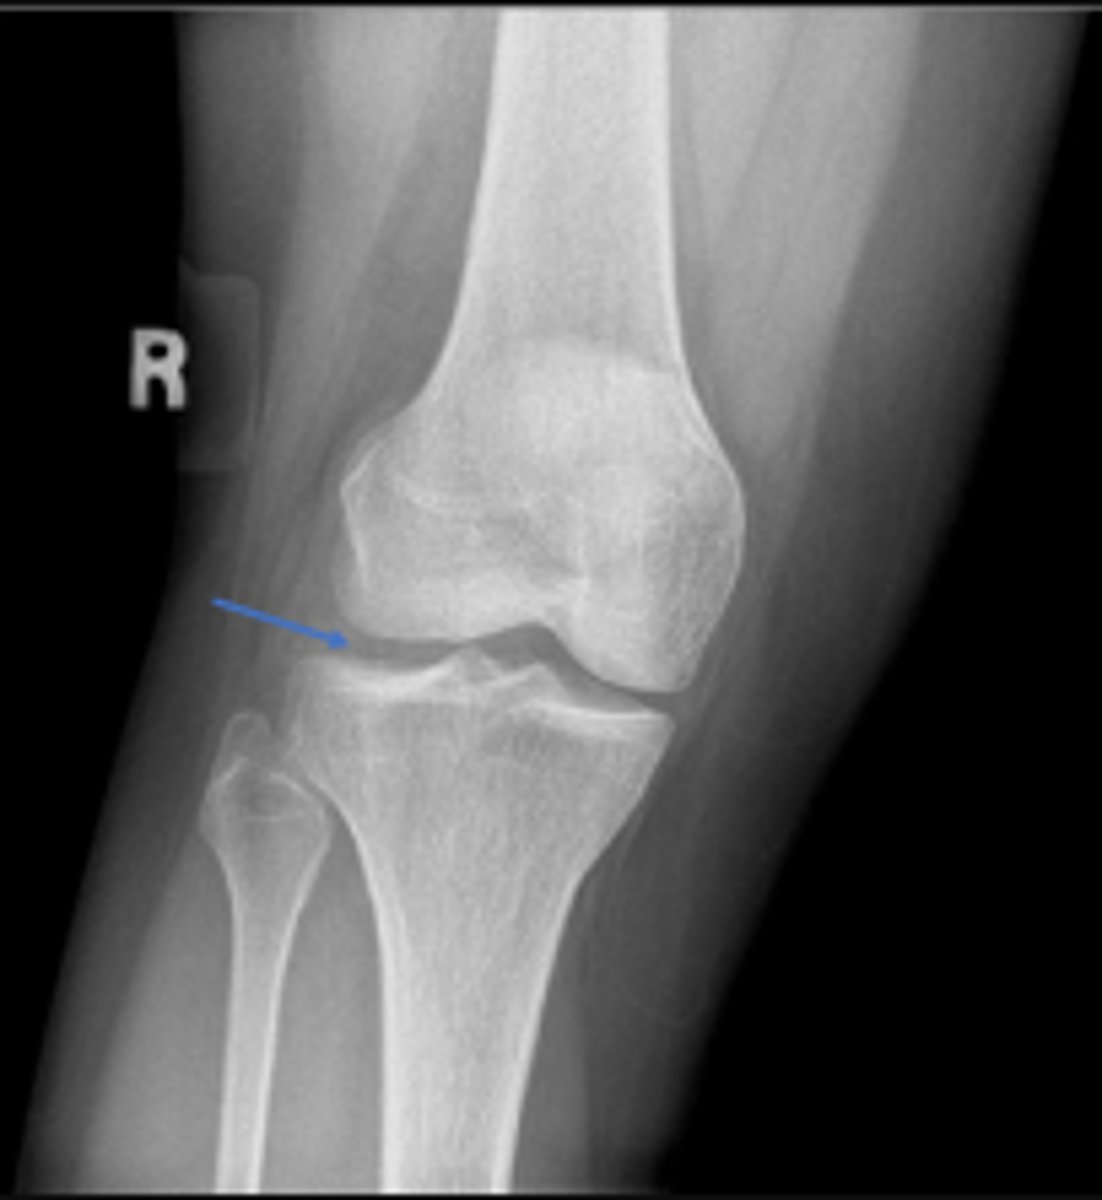

Lateral collateral ligament

What inserts at the location of the blue arrows?

Lateral collateral ligament avulsion fracture of

the right knee

What is the most significant radiographic finding?